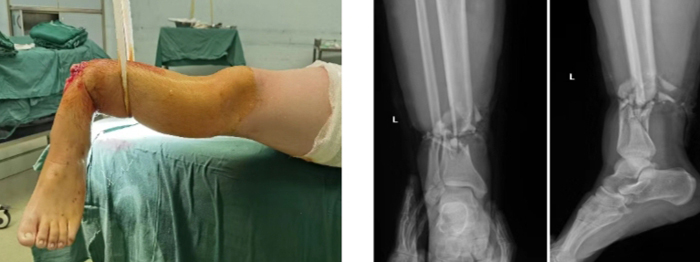

當(dāng)晚,值班醫(yī)師接到會(huì)診電話(huà):患者趙某,男,29歲,因鋼板砸傷致左小腿離斷2小時(shí)急診入院。經(jīng)初步評(píng)估,患者傷口遠(yuǎn)端組織離斷,僅少許皮膚相連,遠(yuǎn)端肢體無(wú)血運(yùn),創(chuàng)口內(nèi)組織毀損嚴(yán)重。經(jīng)與患者及其家屬充分溝通后,開(kāi)通急診綠色通道進(jìn)入手術(shù)室。